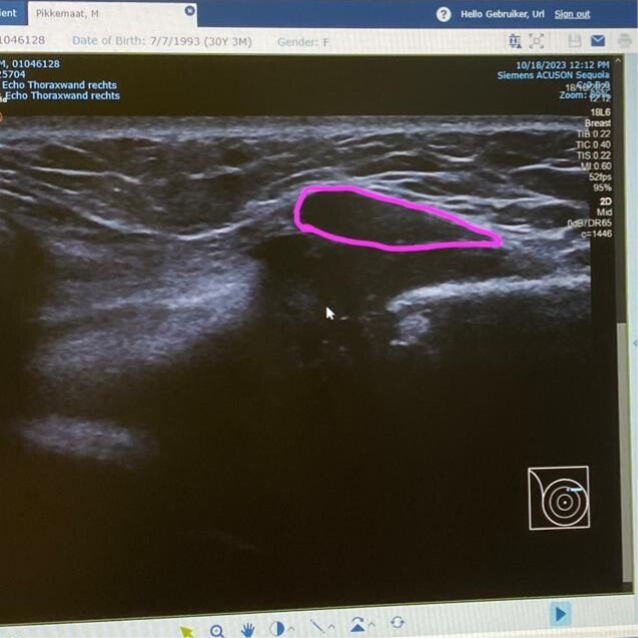

Het was woensdag 18 oktober. Op naar Monro. Kleine Dayn ging mee, want de laatste afspraak was ik daar hoogzwanger en zei ze dat ik de volgende keer de baby mee moest nemen. Zo gezegd, zo gedaan. Zijn eerste lange rit werd het ziekenhuis. Sanne, mijn vriendin was mee, dat hadden we ver voor de afspraak al afgesproken. Zo kon Remco gewoon lekker mais blijven hakselen. De afspraak was met mijn oncologisch chirurg. Zij deed het lichamelijk onderzoek en begon zoals ze altijd begon om te kijken of het haar zo zou opvallen. Toen ze goed ging voelen dacht ze eerst aan opgezette rib aanhechting. Een echo moest duidelijkheid geven. Jammer genoeg gaf het dat niet. Er was wel een massa te zien, maar het kon van alles zijn. De radioloog zei dat een goedaardig gezwel direct te zien zou zijn, en dat was hier niet te zien. Maar het kon wel verder van alles zijn. Het was niet direct misse boel.. Op de foto's zie je hoe het eruit ziet. Het roze lijntje geeft aan wat de verdikking is.